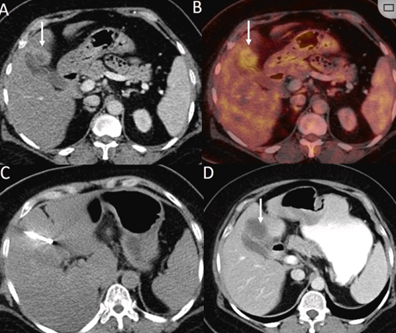

冷冻消融肝包膜下肝细胞癌

(A)动脉期CT图像显示有一个包膜下结节(箭头)。

(B)门静脉期CT图像显示病灶区(箭头)。

(C) 在手术过程中的CT显示一个冷冻探针位于病灶内。

(D)消融后,术后1个月影像CT显示完全消融。

胆囊附近转移灶(来自子宫颈癌)的冷冻消融术

(A)门静脉期 CT 图像显示胆囊附近有病变(箭头)。

(B) PET-CT 图像显示病变处(箭头)。

(C) 手术过程中CT 显示冷冻探针位于病灶内。

(D)消融手术后 1 个月CT 显示完全消融。